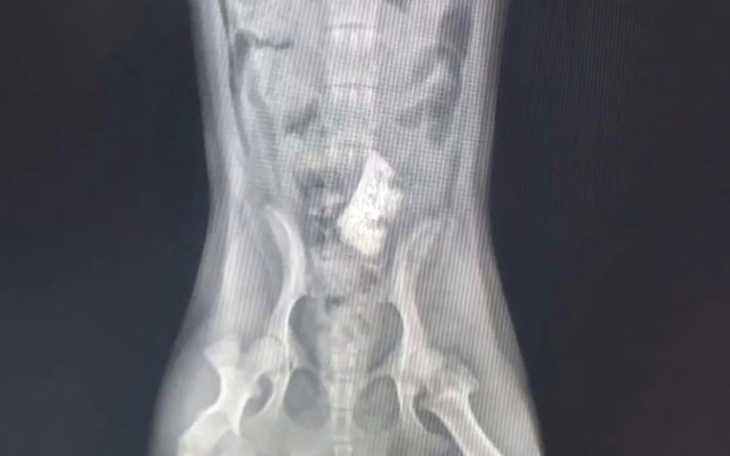

Bardzo proszę o pomoc dla mojego Happiego, który potrzebuje operacji po zaatakowaniu go.